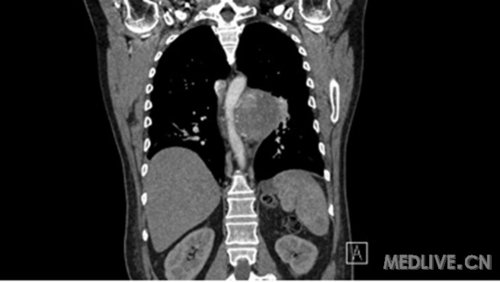

TitleBig, hypervascular paraspinal ganglioma, eroding thoracic vertebrae and ribs

大的富含血管的脊椎旁神经节瘤,侵袭胸椎和肋骨

Description: CT scan image of a huge paraspinal ganglioma extending from T4 to T9 and eroding T7 and T8 vertebrae and ribs, in close proximity to aorta and left main bronchus but not invading them.This paraganglioma was found to be hypervascular on spinal angiography.

CT扫描图像,一个巨大的脊椎旁神经节瘤,从T4到T8脊椎,侵袭了T7、T8脊椎和肋骨,非常接近主动脉和左主支气管但并未侵犯,脊髓血管造影发现这个神经节瘤富含血管。

2. Paraspinal ganglioma, Coronal CT scan

脊椎旁神经节瘤 CT冠状位扫描